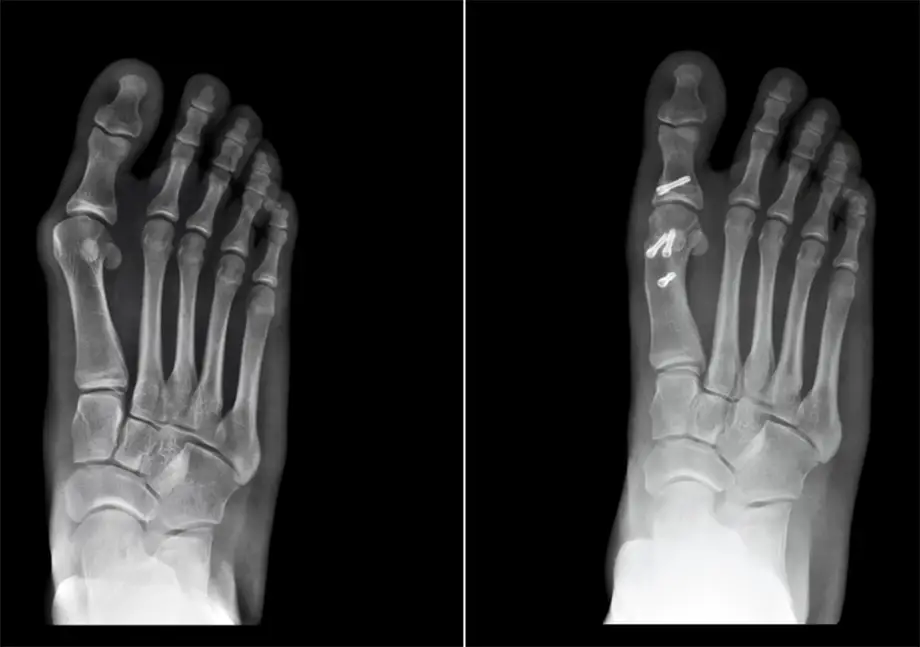

Hallux valgus – diagnostic

Monturile pot fi diagnosticate in timpul examenului clinic, deformarea fiind atat de usor vizibila. Probabil ca, in timpul consultului, medicul te va ruga sa misti degetul mare de la picior pentru a-i evalua flexibilitatea si e posibil sa recomande si efectuarea unei radiografii pentru a putea estima obiectiv gravitatea afectiunii.

• Osteotomia, care consta in efectuarea unor mici taieturi la nivelul oaselor afectate, cu scopul realinierii acestora. Osteotomia este urmata de montarea de suruburi sau placute pentru fixarea osoasa si de proceduri care implica tesuturile moi, pentru realinierea finala;